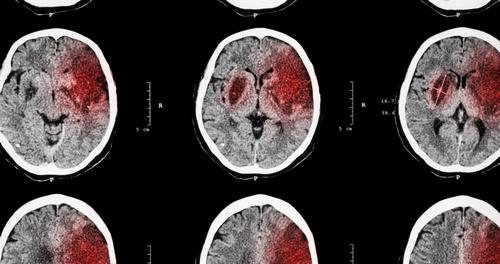

На основе различий в патогенезе выделяют ишемический и геморрагический инсульт. В первом случае удар возникает из-за дефицита кровоснабжения, вызванного нарушением циркуляции крови в определенной зоне мозга, ее некрозом.

Геморрагический характеризуется прорывом сосудистой стенки, истечением крови в мозговые области через образовавшиеся отверстия, формированием отеков и гематом.

Показательным в целях определения диагноза считается МРТ. На полученных снимках видны границы пораженной области, кровоизлияния.